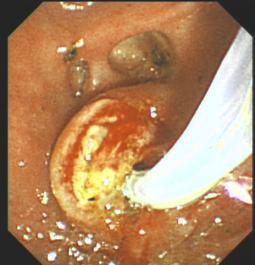

膽石癥ERCP治療